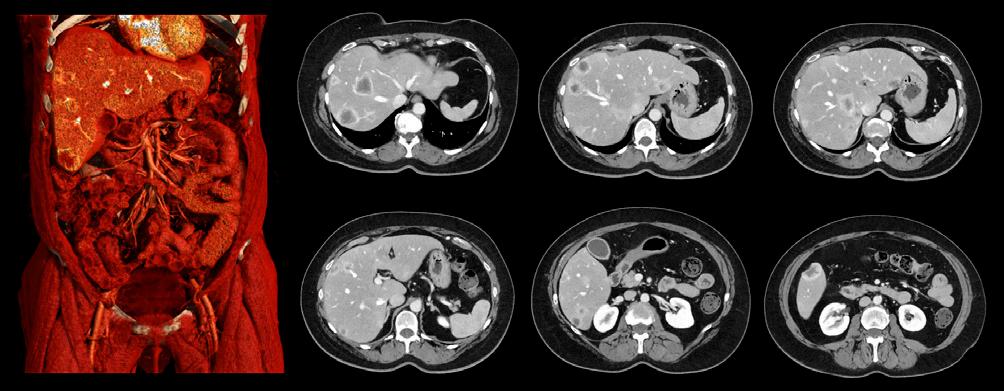

0.5 mm slice thickness PIQE 1024 abdominal images showing increased spatial resolution in this patient with liver lesions.

“The benefit of PIQE 1024 is that it gives us much higher spatial resolution without increasing radiation dose. As it improves spatial resolution, we can image coronary arteries with calcification and stents and we can reduce blooming artefacts. We’ve only had it five weeks, but we are much more confident in our diagnosis because the resolution is much higher,” Dr. Bull added.